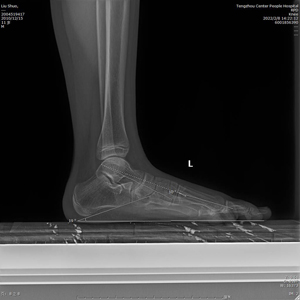

術(shù)前X線示:左足平足并副舟骨?;颊呓?jīng)過足跟墊等保守治療效果不佳,潘維亮主任醫(yī)師主持全科醫(yī)護人員術(shù)前討論一致決定為患者實施全麻下距下關(guān)節(jié)制動術(shù)。

(術(shù)后X線)